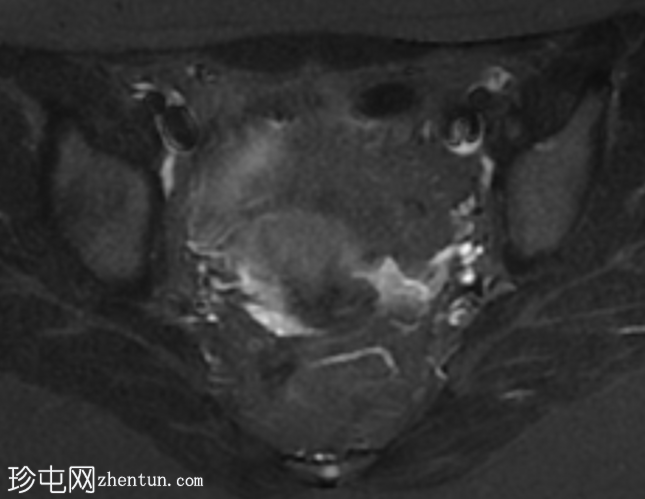

轴位

T2加权像

子宫体积较小,最大横径、前后径和头尾径均为3.0 x 3.0 x 2.7 cm。子宫体与宫颈的比例为1.3:1。子宫无明显分区结构。

双侧卵巢发育不良,无卵泡活动。